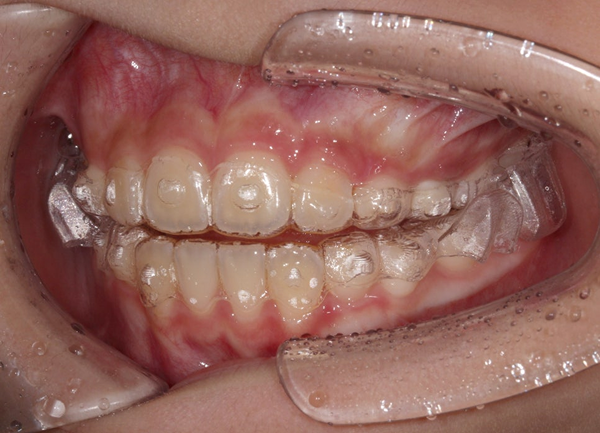

나이 : 12세

성별 : 남자

내원 이유 : 윗니가 뻗어 있다

치료방법 : 턱교정(1차교정) 엑티베이터 with 헤드기어

치료시작 : 2024년 7월

치료종료 : 2025년 11월

치료기간 : 1년 4개월

1년 4개월 간 이루어진

턱교정치료가 끝났습니다.

아래턱이 이쁘게 나왔고

윗니와 아랫니의 앞뒤 차이가

정상 범위 내로 줄어들었습니다.

발치교정을 요하지 않는

상태로 만들었습니다^^